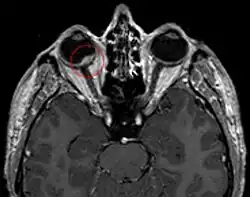

Radiochirurgie

Aderhautmelanom-Patienten, die mit Radiochirurgie behandelt werden, durchlaufen in der Regel ein standardisiertes ambulantes Verfahren. Direkt nach der Retrobulbär-Anästhesie werden ein Kontrastmittel-MRT (Magnetresonanztomographie) sowie ein planungsrelevantes CT (Computertomographie) erstellt. Auf Basis dieser Bilddaten wird das Zielvolumen des Tumors bestimmt und die günstigen Einstrahlrichtungen sowie die Dosis berechnet. In Publikationen wird meist von einer Dosis von median 20 Gy (18 bis 22 Gy) berichtet, abhängig von Lage und Größe des Tumors. Die radiochirurgische Behandlung erfolgt ambulant und ohne Fixierung des Patienten in einer einmaligen Sitzung.